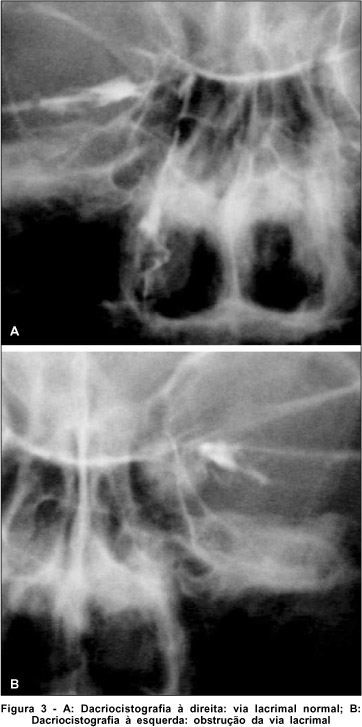

A propedêutica da via lacrimal foi normal do lado direito e apresentava obstrução baixa do lado esquerdo, no qual o saco lacrimal mostrava-se bastante dilatado (4+/4) observado através de dacriocistografia (Figura 3).